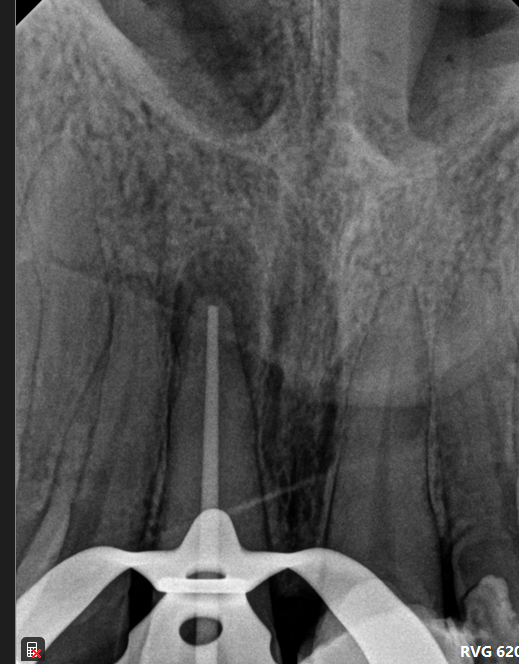

Case: RCT on Tooth #19

35-year-old female, Spanish-speaking, no past medical history.

Dx: Pulp necrosis and symptomatic apical periodontitis with PARL (#19).

Tx: Root canal therapy.

Reflection

The main challenge was the patient’s TMJ discomfort—she had trouble keeping her mouth open and needed multiple breaks. CBCT showed the mesial canals were converging apically, which helped guide shaping. Unfortunately, the distal canal appeared slightly overextended on the final image, reminding me of the importance of precise working length control, especially in cases with limited access.